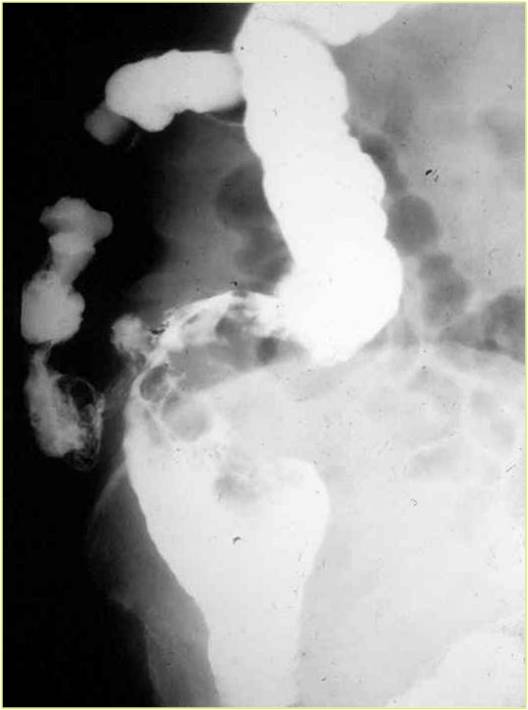

Image

Fig.26.: Napkin ring sign (or apple core sign), is a typical presentation of colon tumors.

Fig.27. Rectal cancer arising from a villous adenoma causes a rugged contour and an extensive filling defect.